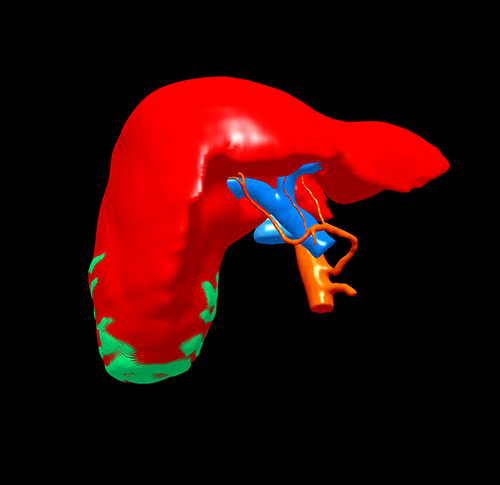

右肝癌-腹腔镜S56肝切除